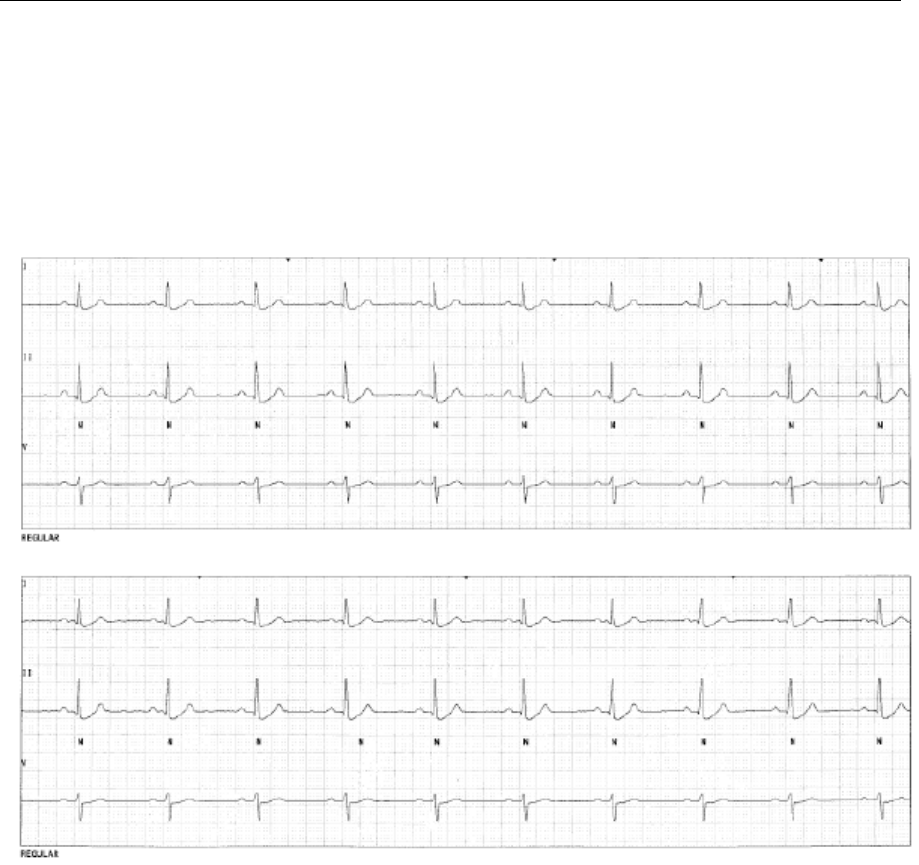

Fig. 18. Regular; Dominant Rhythm ...................................................................................................60

Fig. 19. Low HR; Heart Rate less than Low Rate Limit .....................................................................61